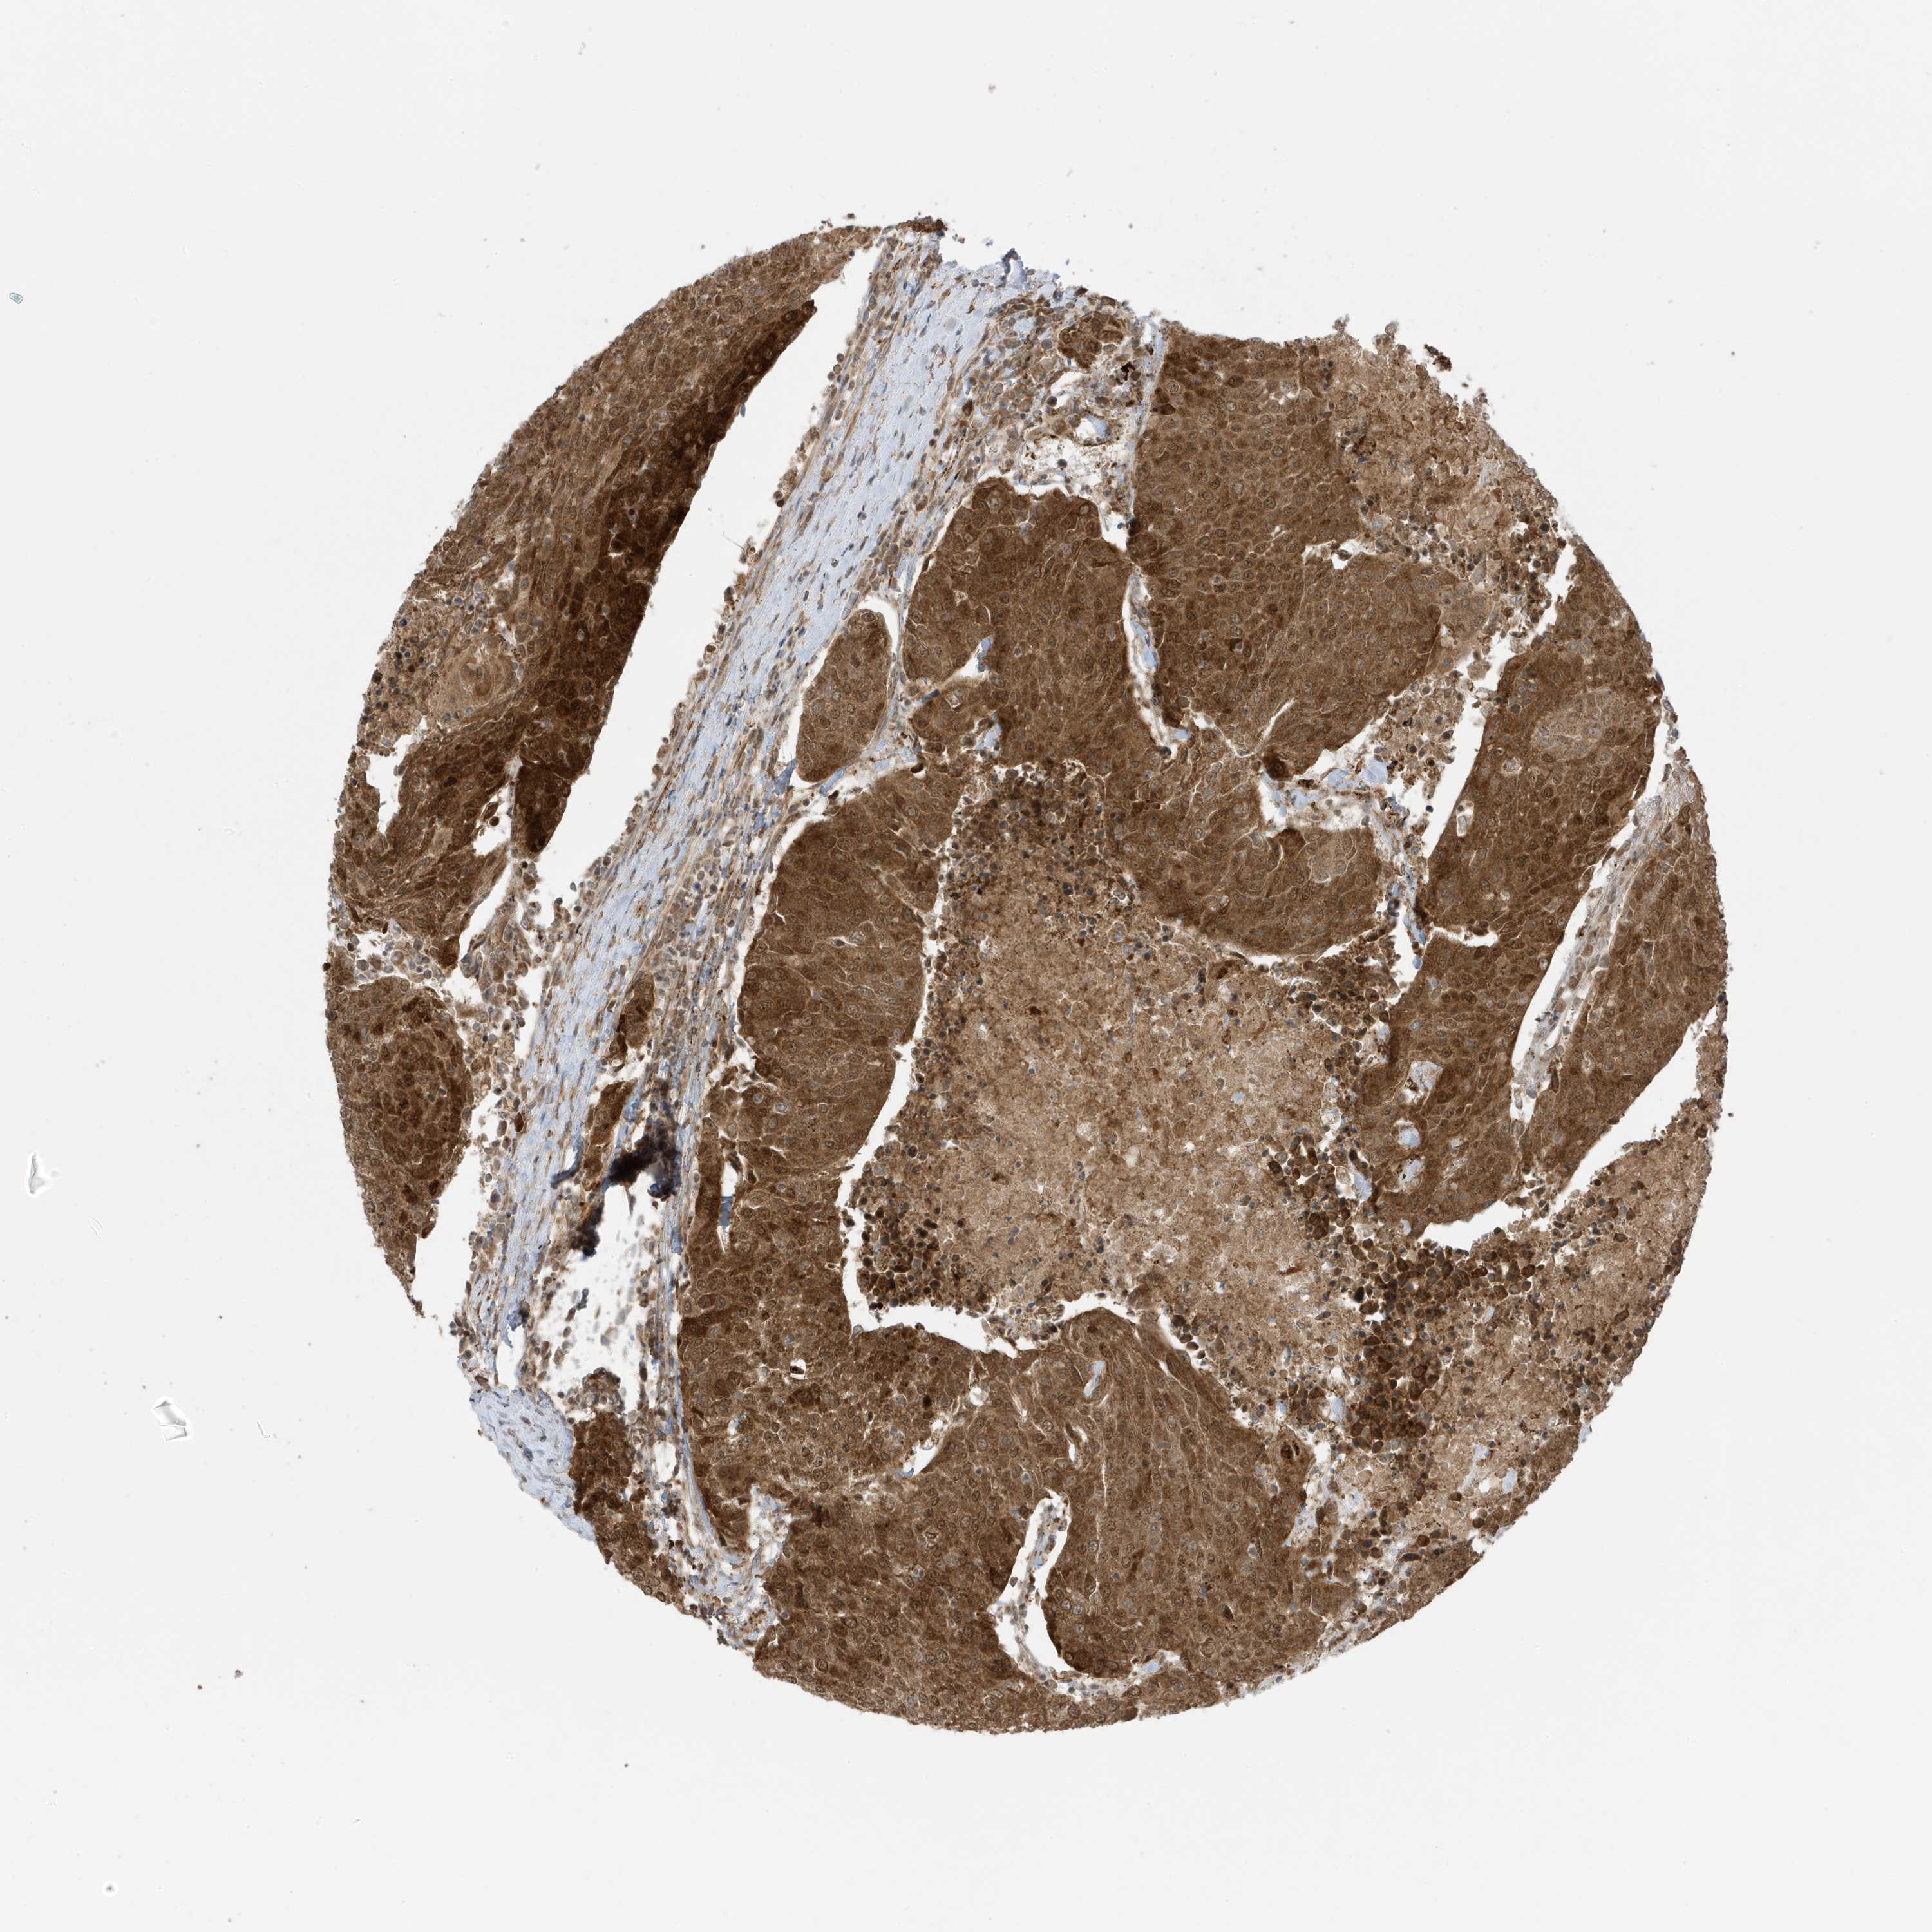

UROTHELIAL CANCER - Protein expressioni

A mouse-over function shows sample information and annotation data. Click on an image to view it in a full screen mode. Samples can be filtered based on level of antibody staining by selecting one or several of the following categories: high, medium, low and not detected. The assay and annotation is described here.

Antibody stainingi

Antibody staining in the annotated cell types in the current human tissue is reported as not detected, low, medium, or high, based on conventional immunohistochemistry profiling in selected tissues. This score is based on the combination of the staining intensity and fraction of stained cells.

Each image is clickable and will lead to virtual microscopy that enables deeper exploration of all samples and also displays staining intensity scores, fraction scores and subcellular localization as well as patient and tissue information for each sample.

Antibody HPA035399

Staining

High

Medium

Low

Not detected

Intensity

Strong

Moderate

Weak

Negative

Quantity

>75%

75%-25%

<25%

None

Location

Nuclear

Cytoplasmic/membranous

Cytoplasmic/membranous,nuclear

Urothelial carcinoma, Low grade

Urothelial carcinoma, High grade